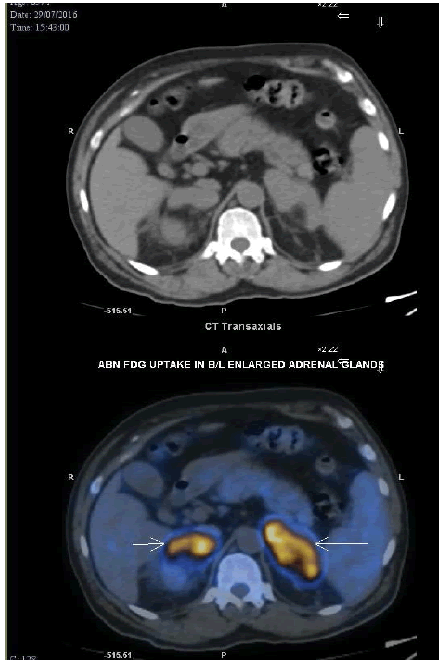

In July 2018, he presented with complaints of headache, swelling, and redness and pain over both lower limbs for two weeks (suggestive of cellulitis). Magnetic Resonance Imaging (MRI) of the brain with whole spine screening showed an enhancing lesion with internal blooming and signal drop in the Apparent Diffusion Coefficient (ADC) involving the posterior aspect of the lateral ventricle and splenium of the corpus callosum (Figure 3). Based on this observation, CNS lymphoma was suspected. PET-CT showed FDG uptake in bilateral tonsils and nasopharynx and enhancing lesion in the body of corpus cal-losum with involvement of ventricles which could represent relapsed lymphoma. A stereotactic biopsy of the CNS lesion showed a round cell infiltrate suggestive of large cell lymphoma (Figure 2d). IHC revealed positivity for CD20 and MUM-1 and negativity for CD3, CD10, TdT, CD5, BCL6, Cyclin D1, and c-myc. In addition, a few CD3 positive cells were seen admixed and Ki67 was found to be 50%. Based on the imaging and histopathology, the diagnosis of isolated CNS relapse of lymphoma was made. Chemotherapy with the modified DeAngelis Protocol was initiated (rituximab 700 mg, methotrexate 3.5 g, vincristine 2 mg, procarbazine 150 mg, dexamethasone in tapering doses on alternate weeks with intrathecal methotrexate for 5 cycles) following which he recovered completely. After 5 cycles of chemotherapy, consolidation radiotherapy with three-dimensional conformal radiationtherapy (3D CRT) at a dose of 36 gray in 18 fractions (200 cGy per fraction and 5 fractions a week, dose pre-scribed to 100% isodose line) to whole brain using bilateral opposed portals was given. Radiotherapy was completed in November 2018 and reassessment MRI in June 2019 showed a complete response. Currently, the patient is disease-free and on regular follow-up.

Figure 3: MRI brain which shows CNS relapse